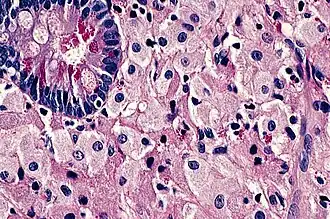

La présence en microscopie optique d'un infiltrat de macrophages spumeux PAS+ est caractéristique.

Aspect des biopsies

Après coloration au PAS, des inclusions sont visualisées dans les macrophages de la lamina propria. Cet aspect n'est cependant ni spécifique ni sensible[9] et le diagnostic peut être aidé par le marquage aux anticorps anti-T. whipplei.